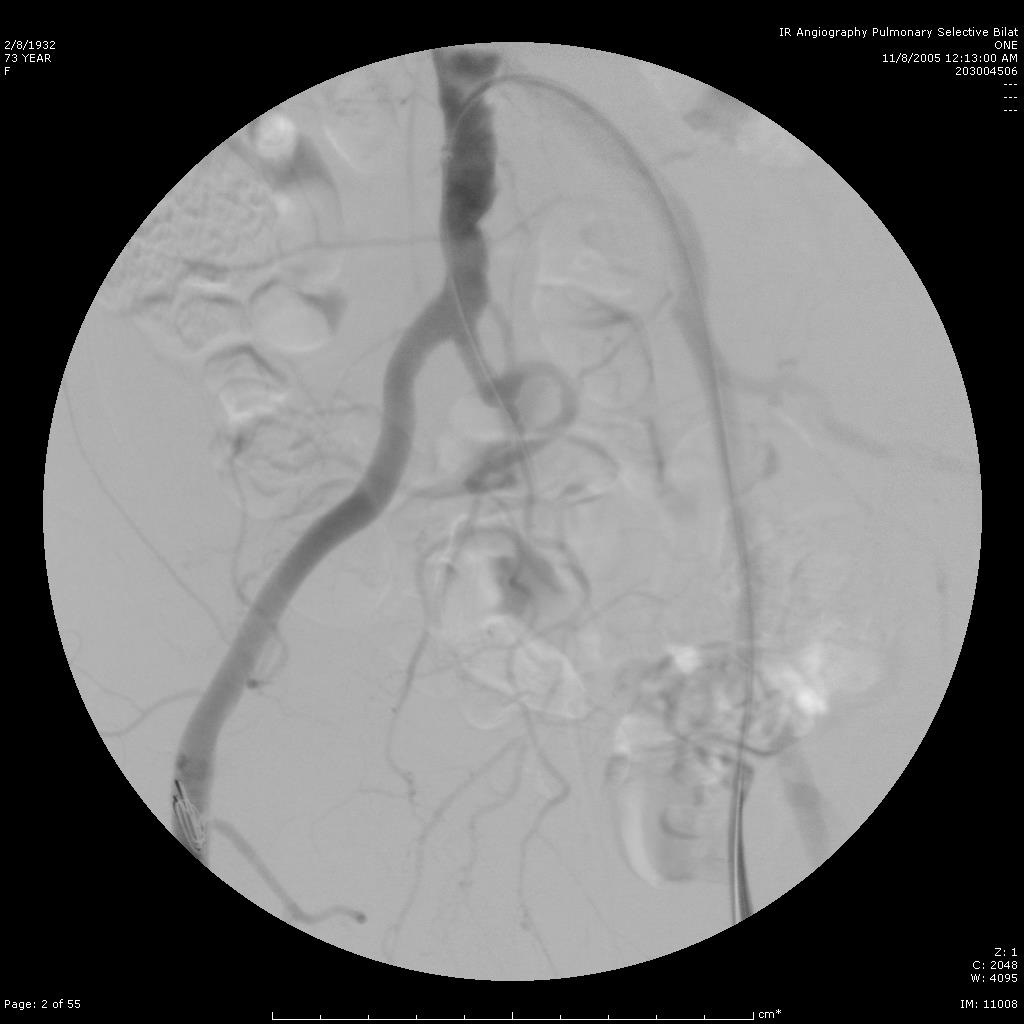

肺动静脉畸形的栓塞(锚定和脚手架技术)

肺动静脉畸形 |

利用锚定技术将弹簧栓子头端释放到肺动脉其中一支后,其余部分释放到血管内 |

栓塞术后造影 |

肺动静脉畸形的栓塞

肺动静脉畸形CT |

肺动静脉畸形血管造影(动脉显影) |

肺动静脉畸形血管造影(静脉显影) |

肺动脉栓塞后 |